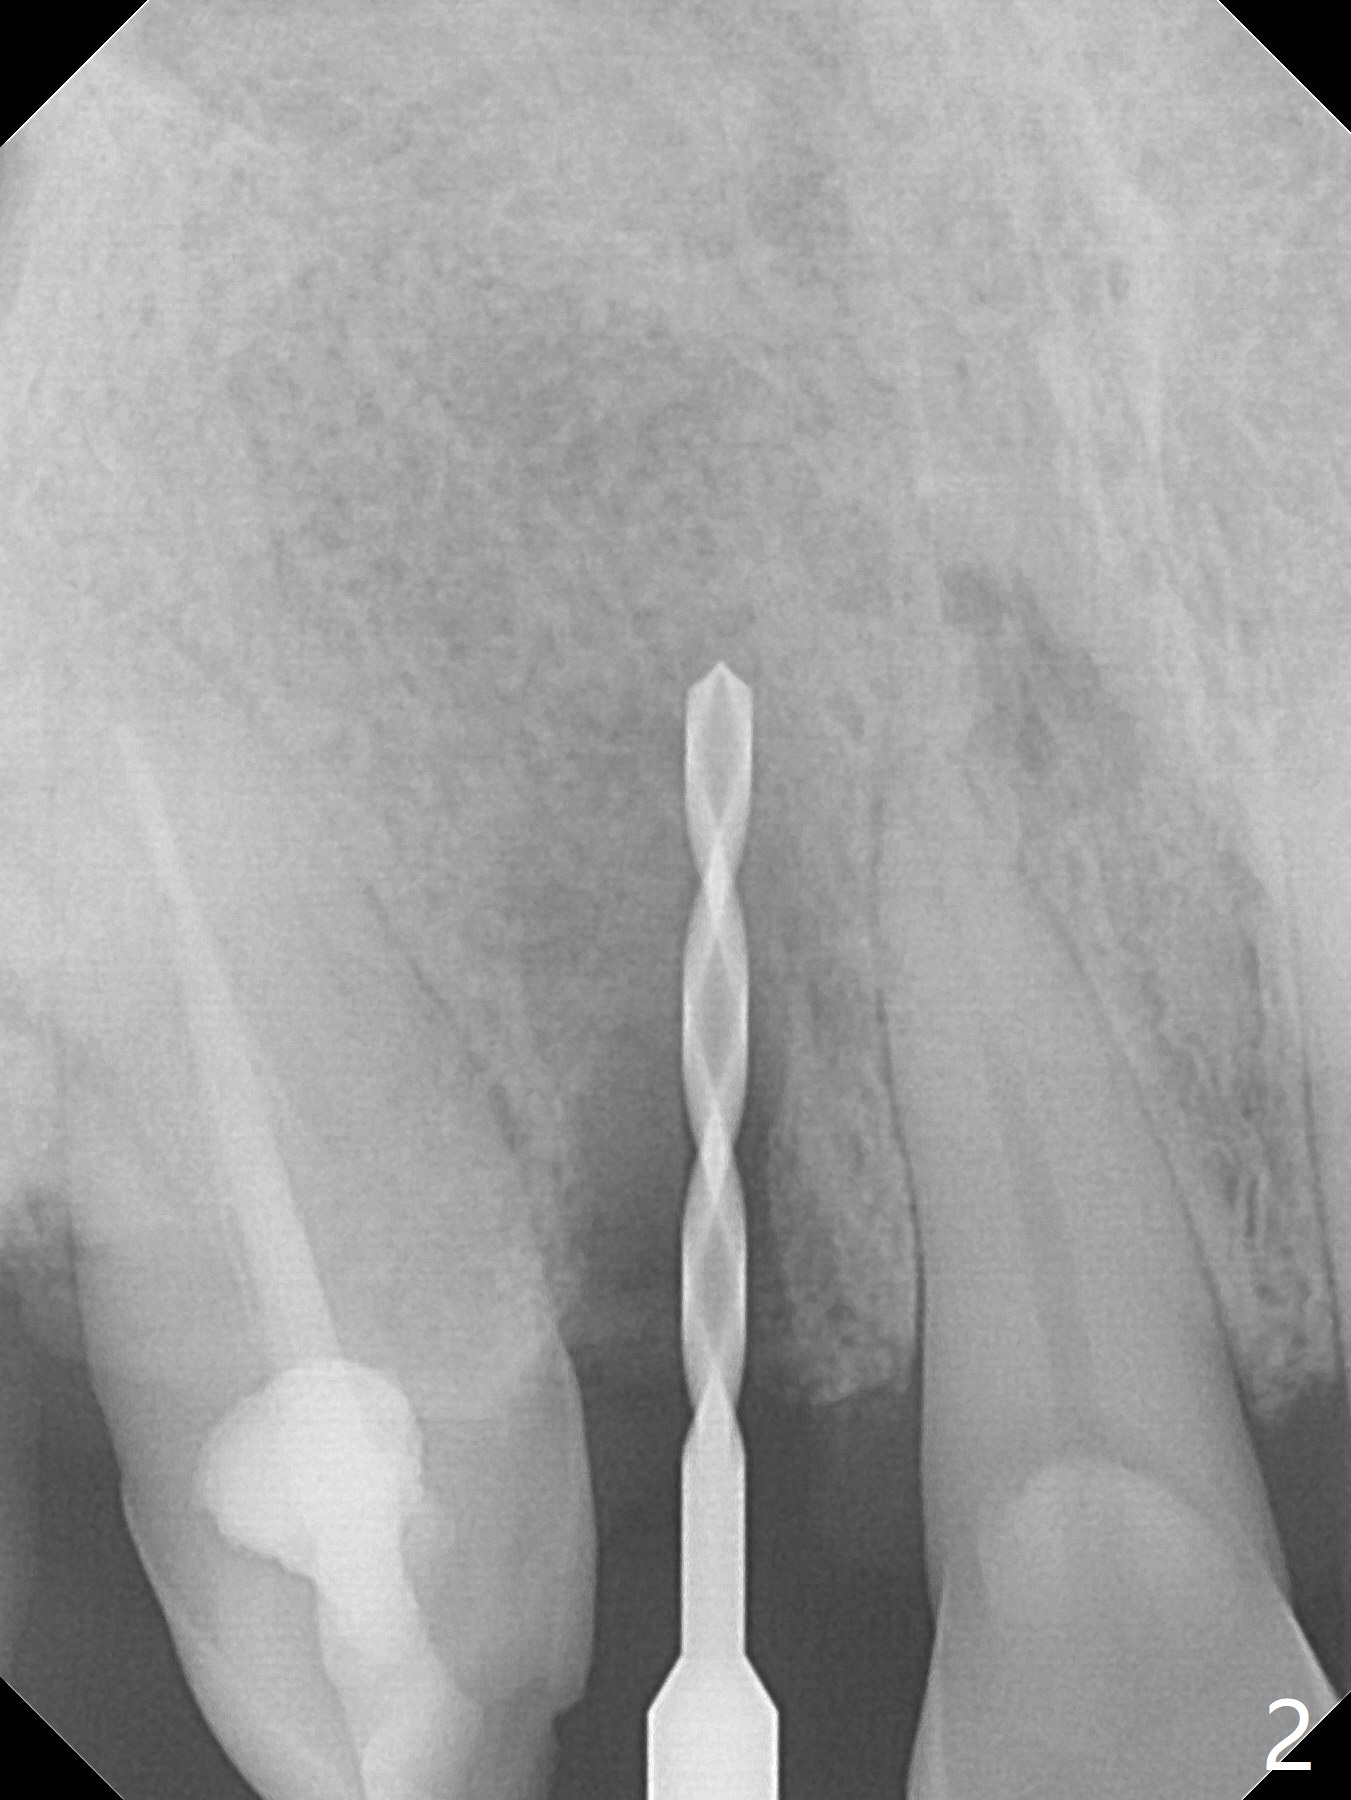

An apical abscess is present when the patient returns for immediate implant at #7 (Fig.1 *); a 2nd challenge is deep bite. After smooth extraction, the apical buccal plate is found to be perforated. Following debridement, a piece of gauze is placed in the apical defect for hemostasis, while osteotomy is initiated palatal (Fig.2). The apical defect seems to be extensive (Fig.3 yellow dashed line). A new trajectory is intended (red arrow) without much success. Before implant placement, bone graft is placed in the apical defect defect area, while a drill (Fig.4 D) is inserted in the finished osteotomy (Fig.5 O). In spite of seemingly large apical defect, the buccal crest bone exists (Fig.4 x). A 3x14(2) mm 1-piece implant is placed with stability; the first round of bone graft is apparently around the apical portion of the implant (Fig.6 *). The coronal end of the implant has to be adjusted several times buccopalatally to accommodate the deep bite. A 2nd round of bone graft following an immediate provisional closes the coronal space of the socket (Fig.7 *). CT will be taken to show the bone graft to repair the buccal plate defect when the patient returns for postop follow-up. In fact the defect is minimal in CT a month ago. The fistula does not disappear 1 week postop, but it is non tender (Fig.8). The patient complains of asymptomatic swelling in the right nostril. CT shows that the large buccal perforation is repaired with large amount of bone graft (Fig.9,10 *). It would be nicer to place the implant slightly more buccal apically (Fig.11 red lines; Fig.12 (preop design)). The buccoapical fistula disappears nearly 1 month postop (Fig.13). The apparently "lifeless" bone graft seems to be harmonious with the surrounding tissue (Fig.14). The periimplant gap reopens with implant mobility nearly 4 months postop (Fig.15), which is related to micro-movement associated with the immediate provisional. The latter is removed. A larger 2-piece implant will be placed in a 2-staged manner if needed (Fig.16). In fact the 3x14 mm straight 1-piece implant (Fig.17) has no mobility when it is retightened, but the trajectory remains buccal. Incision shows that there is no implant thread exposure. A 3x14 mm 15 degree angled 1-piece dummy implant is able to establish the correct trajectory, but there is no occlusal clearance (Fig.18). Micromovement during osteointegration may recreate loosening. Finally using Lindamann bur, the osteotomy is changed so that a 3.5x13 mm 2-piece implant does not need an angled abutment to establish occlusion (Fig.19). There is one palatal thread exposure. Allograft is placed circumferentially, followed by Human Amnion-Chorion Allograft and Collagen Plug. The wound does not heal 8 days postop (Fig.20), as related to the age (79 years old)? The wound appears to heal with a membrane on the surface (Amnion-Chorion one?) 3 weeks postop (Fig.21). The ridge looks wide 3.5 months postop (Fig.22,23). A 4.5x5.5(3) mm appears to be seated incompletely with a gap between the abutment and the implant (Fig.24<). A provisional is fabricated after heavy palatal reduction. Two months later, the provisional fractures. After repositioning the abutment with complete seating and torque (Fig.25), impression is taken. Although the buccal plate is concave, the gingiva remains healthy 10 months post cementation (Fig.26,27).